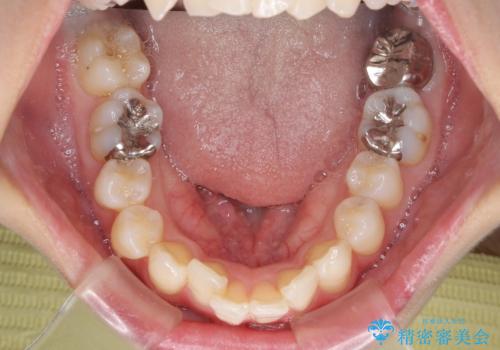

上下の咬み合わせは上顎歯列全体が歯1本分前にずれている状態であり、さらに上顎歯列はV字型に尖っていたため、上下前歯は全く接触していない状態でした。

上顎左右第一小臼歯を抜去して、ワイヤー装置にて口元の突出感を改善するよう矯正治療を行うこととしました。